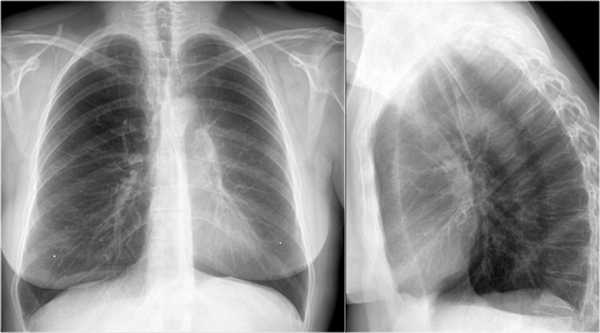

Ателектаз нижней доли правого легкого.

На нижепредставленой рентгенограмме пациента 70 лет, упавшего с лестницы, в плевральной полости определяется скопление жидкости, предположительно являющейся кровью.

Это ателектаз нижней доли правого легкого.

Обратите внимание на правую границу сердца. Правая междолевая артерия не видна потому, как она не окружена воздушной легочной тканью, а закрыта спавшейся нижней долей правого легкого.

Ниже представлены последующие рентгенограммы органов грудной полости того же пациента, на которых ателектаз разрешен.

Обратите внимание на правую междолевую артерию (красная стрелка) и границы правых отделов сердца (синяя стрелка).